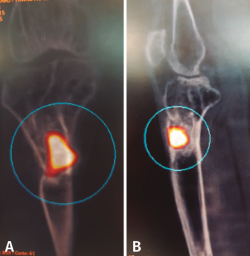

Tras estudio de tomografía computarizada de emisión monofotónica (SPECT-TAC) y gammagrafía con leucocitos marcados, se objetiva foco séptico al nivel del extremo proximal de la tibia (Figura 3).

Figura 3. Estudio de SPECT-TAC-gammagrafía con leucocitos marcados. Se objetiva captación compatible con proceso séptico en el extremo proximal de la tibia.